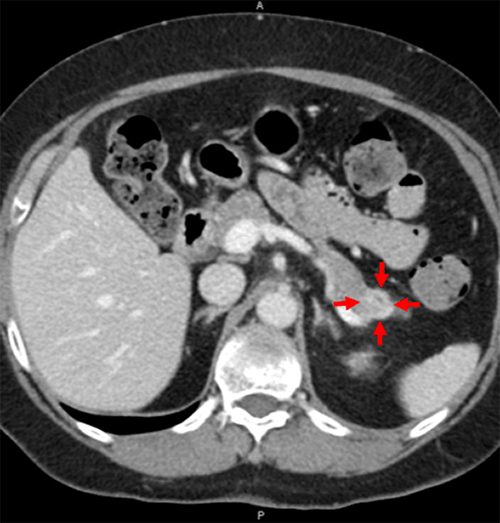

The patient is a 62-year-old female with a history of hypertension, hyperlipidemia, GERD, and gout who presented with abdominal pain and diarrhea for several days. The patient had a CT scan for suspected diverticulitis during prior evaluation at an outside facility that showed concern for a pancreatic tail mass or focal pancreatitis due to peripancreatic inflammatory change. Lipase was 29 U/L, which was within normal limits. A repeat CT scan at our facility revealed a 2.1 × 1.5 cm ovoid mass within the pancreatic tail, demonstrating arterial enhancement and progressive enhancement on portal venous phase imaging (Figure 1). She was referred to a gastroenterologist for endoscopic ultrasound (EUS).

Figure 1. Axial CT Imaging With Multiphase Pancreatic Protocol. Published with Permission

A) Progressive enhancement on portal venous phase and B) arterial enhancement with finding of hypodense lesion (red arrows) in the pancreatic tail measuring 2.1 × 1.5 cm.